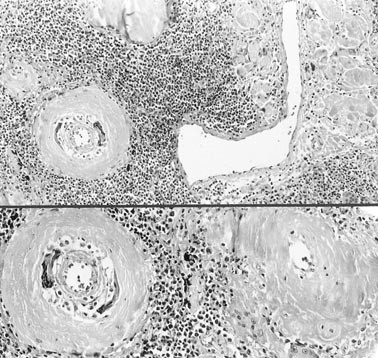

FIGURE 6

Malignant lymphoma: Vascular wall deposits of amyloid were accompanied by a granulomatous reaction. The lymphoid infiltrate in lymphomas was intense and lacked a gradient from the center of the nodular lesions to their periphery (hematoxylin and eosin stain, original magnification, 40 ×, top; 80 ×, bottom).